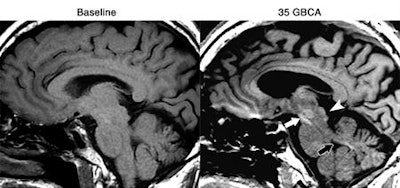

Patients who received more than 35 injections of gadolinium-based contrast agents (GBCAs) had higher levels of signal intensity on unenhanced MR images of the brain, according to a new study published online August 11 in Radiology. But researchers weren't able to find any adverse clinical effects in the individuals.

The group from Weill Cornell Medicine and Columbia University Medical Center found greater signal intensity in the dentate nucleus and global pallidus in patients who had a large number of gadolinium administrations, compared with individuals who had fewer GBCA administrations. Despite the rise in signal intensity, there were no obvious signs that the additional gadolinium caused any harm to patients.

After reviewing the records of one patient who received 34 GBCA administrations at their institution and noticing increased signal intensity beyond the dentate nucleus and globus pallidus, Prince and colleagues pondered the ramifications of a large number of GBCA injections for patients.

All three radiologists found increased signal intensity in the dentate nucleus, globus pallidus, and substantia nigra in all 13 subjects, as well as greater signal intensity in regions such as the posterior thalamus, red nucleus, and colliculi in other subjects. The dentate nucleus also had the greatest mean increase in signal intensity, nearly double that of the globus pallidus and posterior thalamus.

The increase in signal intensity in the dentate nucleus was much more dramatic than what Kanda et al found in the same area, Prince and colleagues noted. The current research also differed from previous studies in discovering greater signal intensity in other brain regions.

"When there are more than 35 gadolinium injections, we are seeing more locations in the brain that show signal change beyond the dentate nucleus and global pallidus," Prince said.